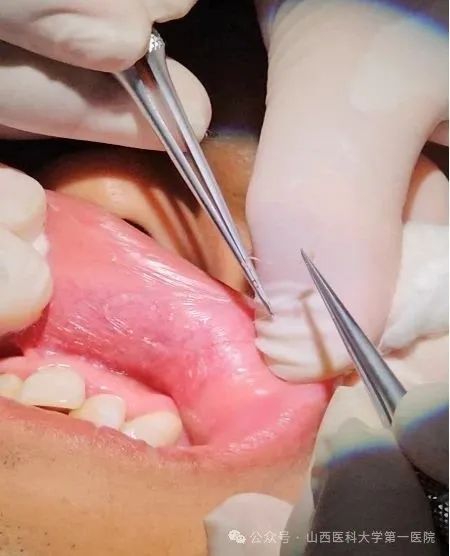

赵玮医生与口腔外科落全祥医生协作,取出一条乳白色、细长、质硬的活体线状虫体。虫体取出后,患者不适症状缓解。经将虫体图片交予检验科同事,根据形态学特征及长度(55毫米),初步判定为美丽筒线虫雌虫(文献记载:雌虫长32.0-68.8mm)。后经山西医科大学寄生虫教研室张杰老师进行形态学鉴定,确认为美丽筒线虫,感染病科窦永清主任医师在诊疗期间也提供了帮助。